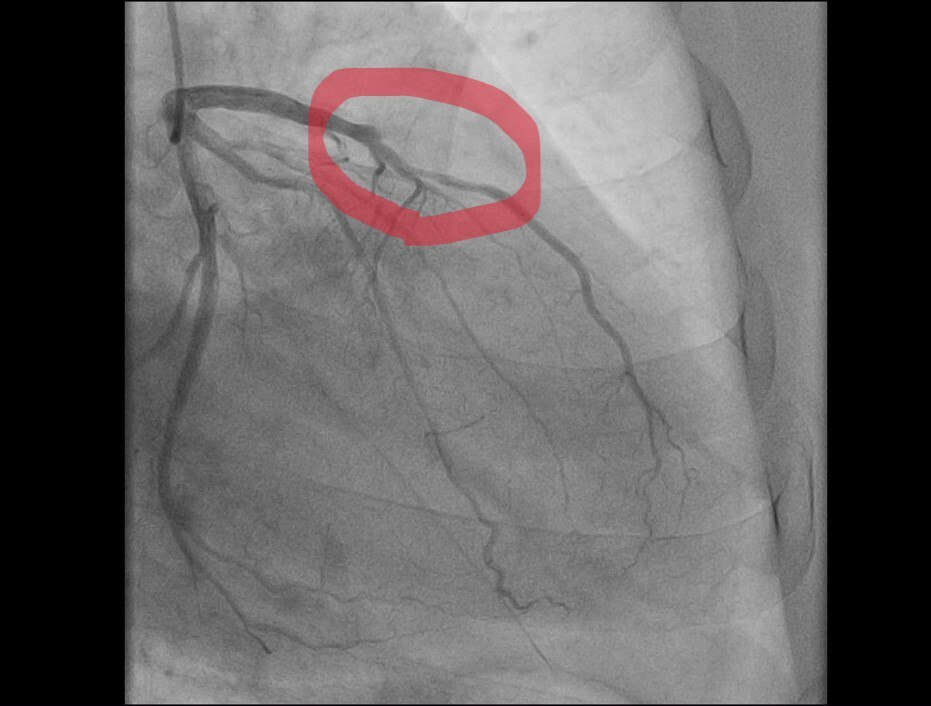

«Пациент, мужчина 59 лет, поступил после того, как почувствовал острую боль в груди во время уборки снега. Бригада „скорой“ диагностировала острый инфаркт миокарда. В ходе обследования была выявлена острая тромботическая окклюзия передней межжелудочковой артерии — сосуда, который неофициально называют „артерией вдов“ из-за высокой летальности при его поражении», — рассказали в балаковской больнице.

Операционная бригада выполнила экстренное стентирование артерии, в результате чего её проходимость была полностью восстановлена. После этого пациента выписали для продолжения реабилитации на амбулаторном этапе.